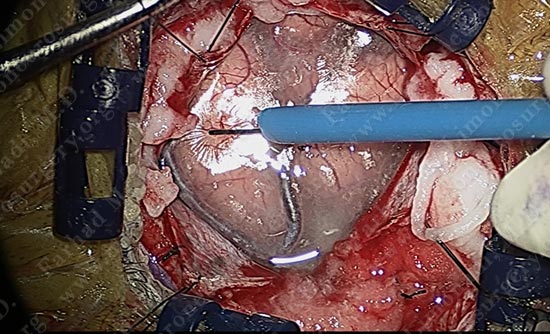

Using a scalpel, the arachnoid between the motor strip and adjacent gyrus is carefully opened without damaging the adjacent vessel.

Micro-instruments are utilized in opening the interval between the two gyri underneath which the tumor is hidden. Patient is being examined in short intervals.